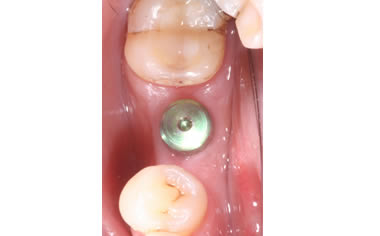

More back teeth replaced by dental implants

Case Five (4 images)